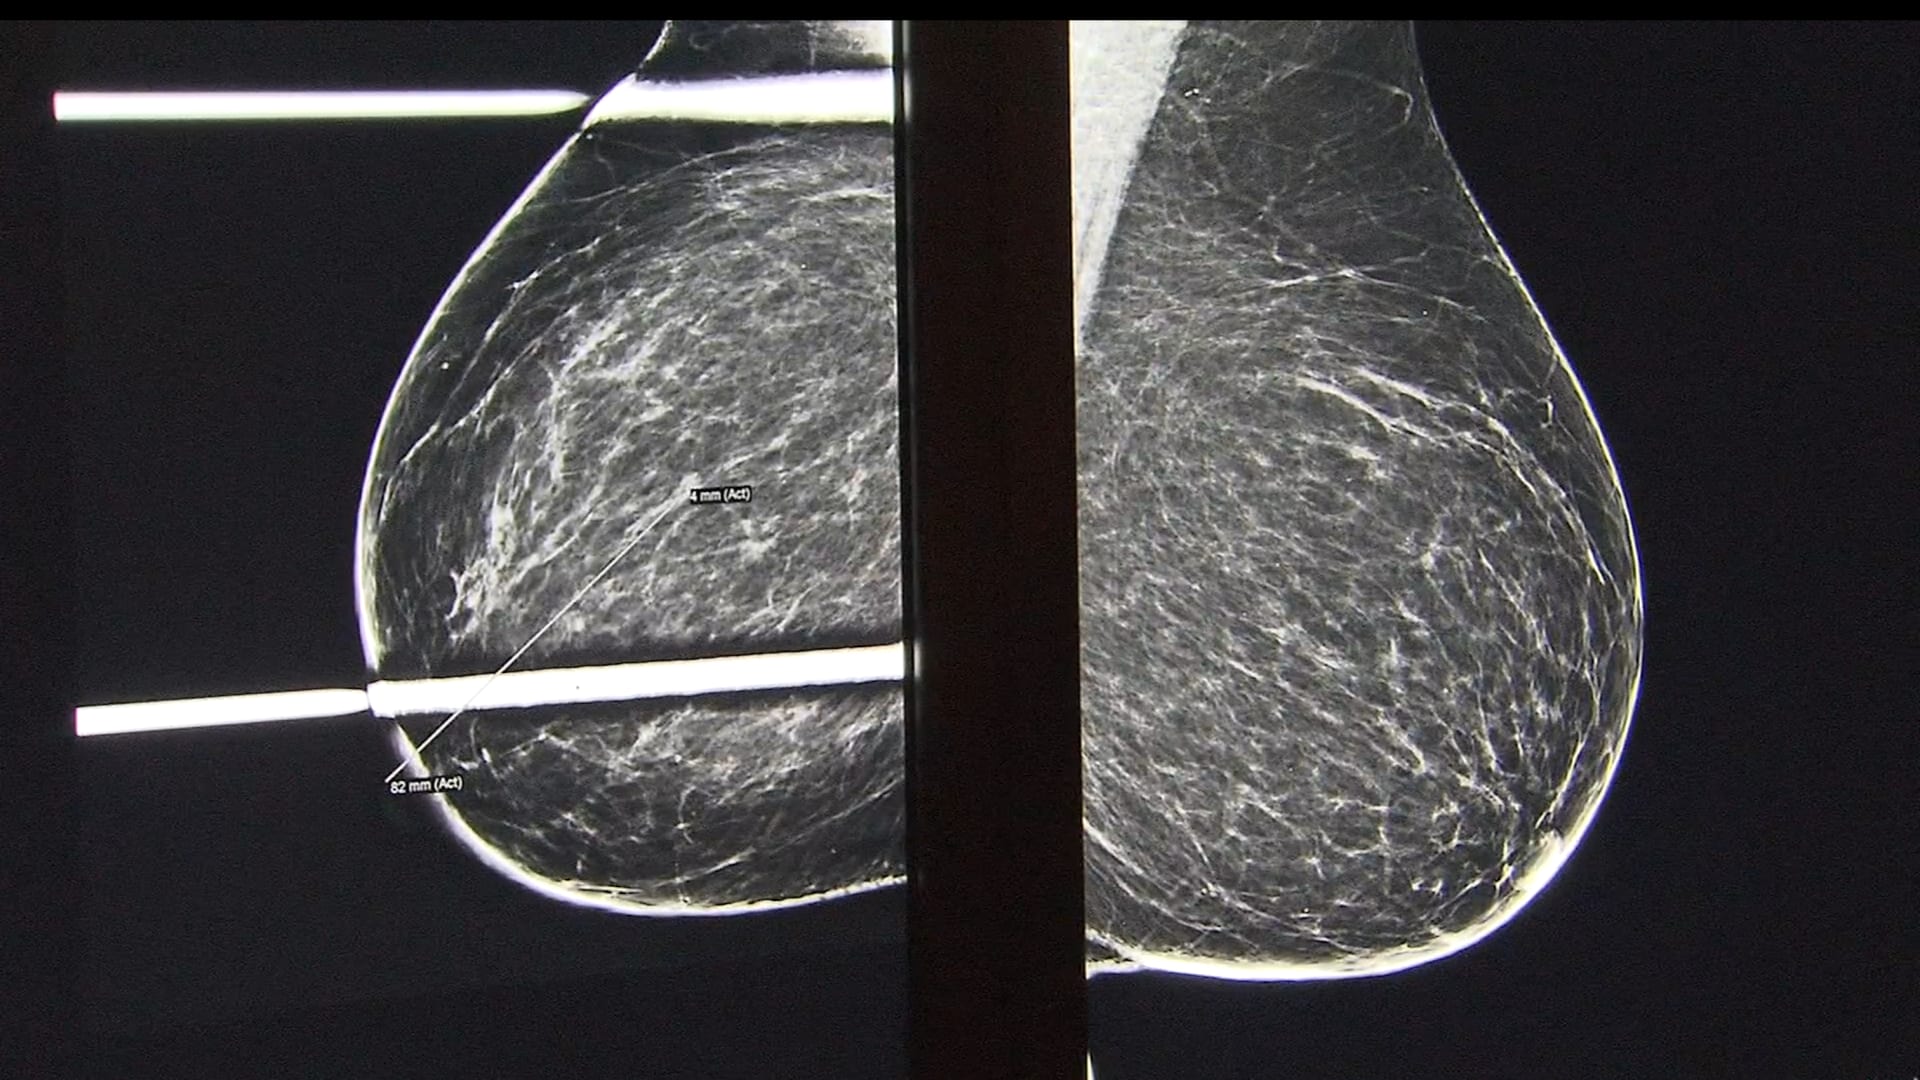

الطفلة فايلا وايت البالغة من العمر عامين، شُخِّصت بورم عصبي خبيث من الدرجة الرابعة، ونُقلت من منزلها في ميشيغان إلى مستشفى موت للأطفال في آن أربور لتلقي العلاج. بعد مشاركة جدتها لمعاناتها، تبرع المجتمع بأكثر من 50 هدية لها، ونقلها ثلاثة من رجال الشرطة لمسافة 965 كيلومترًا تقريبًا لتصل إلى المستشفى، في رسالة دعم تؤكد أن الطفلة ليست وحدها في معركتها مع المرض.